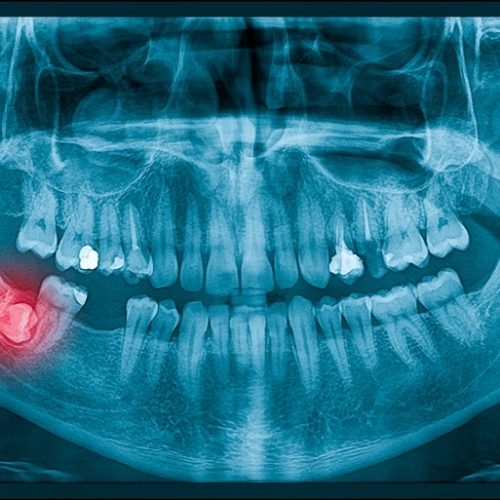

​Fjernelse af visdomstænder, rodspidsoperationer, operationer af cysterog isætning af implantater er blandt de indgreb, vi klarer her på tandlægeklinikken:

• En visdomstand, der ikke er vokset rigtig frem, skal eventuelt fjernes, så den ikke danner betændelse eller skader på nabotænderne.